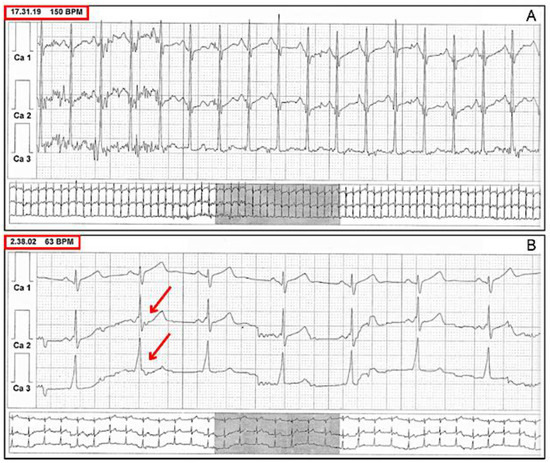

6. Risk Stratification

7. Stress Test Pitfalls